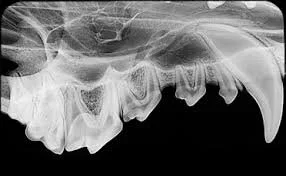

Tannrøntgen

Vi har også digital tannrøntgenmaskin som benyttes ved skader og sykdom i munnhulen. På lik linje med mennesker burde det alltid tas røntgenbilde av munnen ved tannbehandling. Det finnes en rekke lidelser i tannrøtter og beinvev som ikke kan oppdages kun ved inspeksjon av munnen alene. Hos oss er tannrøntgen av hele munnen inkludert i prisen ved vanlig tannbehandling.